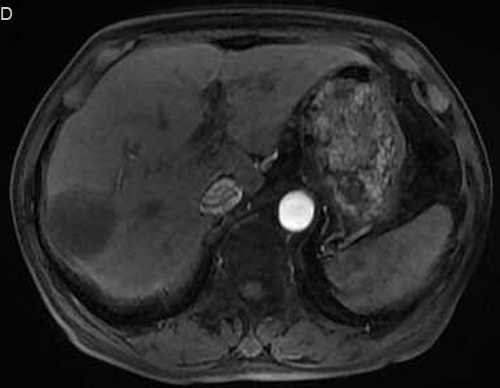

According to the imaging findings from before and after therapy, excluding the one case that was lost to follow-up, there were 11 PR cases (42.3%), 10 SD cases (38.5%), 5 PD cases (19.2%), and no CR cases. The efficacy rate was 42.3% (Figures 1 and 2).

Figure 2: Eighty six-year-old male with a huge hypervascular metastatic pancreatic neuroendocrine tumor treated with multiple cycles of chemotherapy. A. Gd-enhanced T1WI revealed a round enhanced tumor of the right lobe in the arterial phase. B. Tumor staining during arterial phase of DSA: The tumor was nourished by the branches of the right hepatic artery. C. Tumor staining disappeared after TACE therapy. D. Gd-enhanced T1WI 2 image months after drug-eluting microspheres loaded with oxaliplatin chemoembolization showed signal reduction indicating resorption without enhancing residual or recurrent tumor mass.